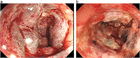

1. 虚血性大腸炎とは、動脈硬化や腸管内圧の亢進による腸管の虚血により生ずる粘膜傷害である。

1. 本症の病因は不明であるが、血圧低下、動脈硬化などの血管側因子と腸管内圧亢進などの腸管側因子がからみあい、腸粘膜あるいは腸管壁の血流低下を引き起こして虚血状態を作ると推定されている。